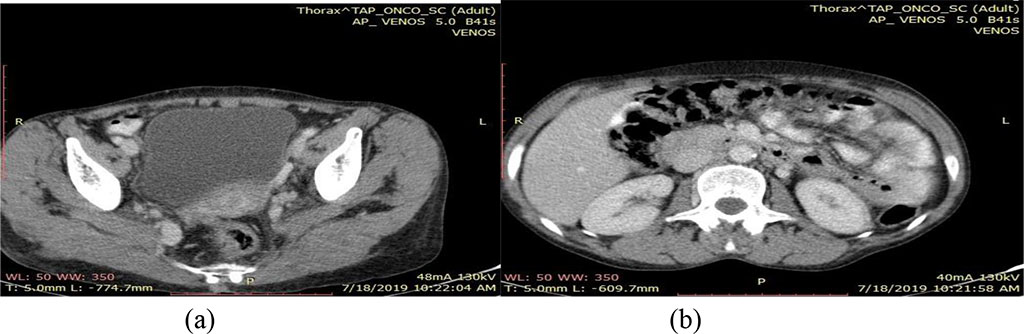

Contrast soft tissue cervical, thoraco-abdominal and pelvic computed tomography reveals 8 mm left cervical lymph nodes, normal-sized kidneys with physiological secretion and excretion, no retroperitoneal lymph node enlargement and no discernable lung and liver pathological changes. The cervix presents a homogenous, iodophil image that is smaller than what was previously found at CT examination (Fig.4).

Fig.4. CT scan July 2019 - (a) Heterogeneous cervical image

and (b) normal sized kidney with physiological secretion and

excretion

Source: Authors' own work